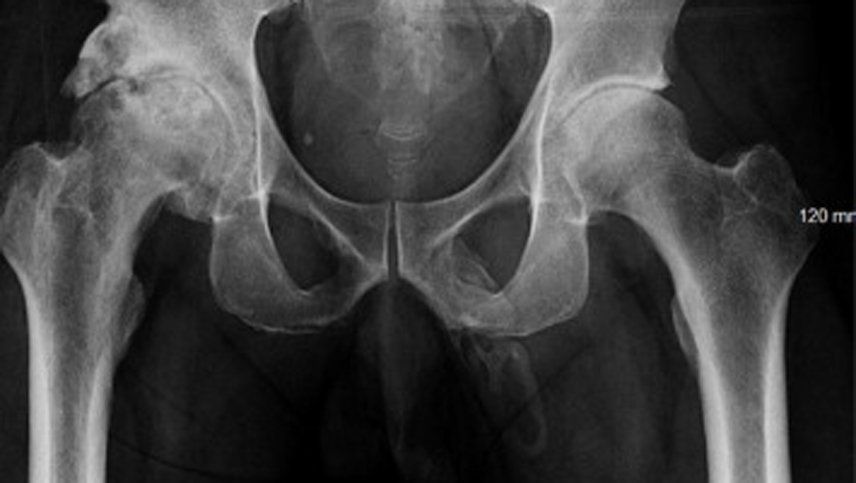

Al realizar placas de la zona pélvica para verificar el estado de la cadera, los médicos notaron que algo andaba mal con su pene. En las imágenes, este paciente literalmente parecía tener un hueso dentro de él aunque como sabemos, esta parte del cuerpo carece de estructuras óseas.

De acuerdo con un artículo publicado por la revista Urology Case Reports, el Hospital Lincoln reportó que el paciente llegó con dolor en una rodilla y comenzaron a practicársele los exámenes que finalmente mostraron una extensa calsificación en el órgano reproductor del hombre, aunque él ni siquiera sospechaba que algo anda mal.

Debido a lo extraño del caso, los médicos especialistas tardaron varias semanas en determinar que el paciente sufre de una condición llamada osificación del pene, que consiste justamente en el desarrollo de tejido óseo en el órgano a causa de alojamiento de sales del calcio en sus tejidos blandos.